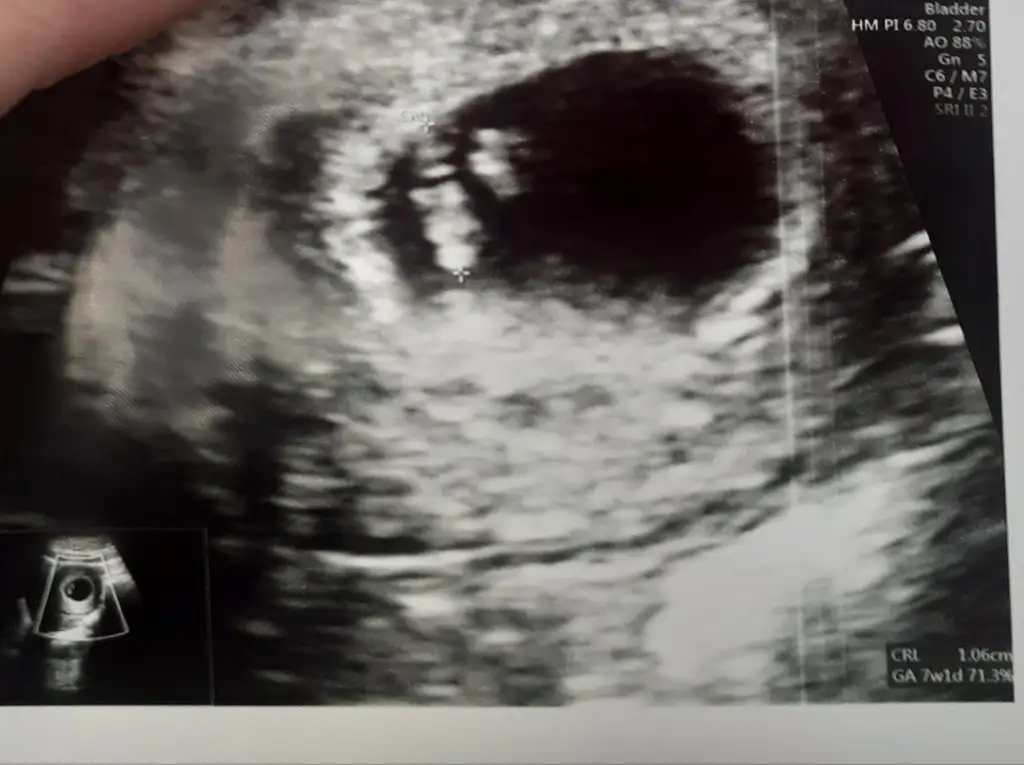

Tabloda neden yoksunuuuzzzzz, bilgilerinizi gönderin ki ekleyelim sizi de :)kızlar ben sabah çok kötü hissedince en yakındaki hastaneye gittim bulantı hapı yazsın diye.prilam yazdı doktor. sabah iki akşam iki adet. biraz fazla sanki. ama gözümü açamıyorum bulantıdan resmen. bebişi de ilk kez görmüş oldum. 6+3 dedi. uygulamaya göre 7. bu 10. haftaya kadar böyle değişkenlik gösterebilir dedi. fotoyu da ekliyorumEki Görüntüle 3424467